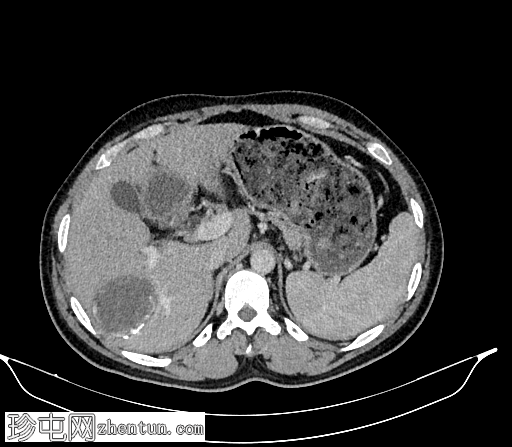

轴位

平扫

肝脏VII段可见一边界清晰的囊性病变,内部有分隔,囊壁可见钙化。

右肾中央部分(肾门)可见一囊性病变,中心可见基质,周围可见子囊。该病变与肾盂肾盏无交通。病变周围可见两处高密度影,位于上、中肾盏,无法区分是结石还是病变壁钙化。另可见上极肾盏中度扩张。